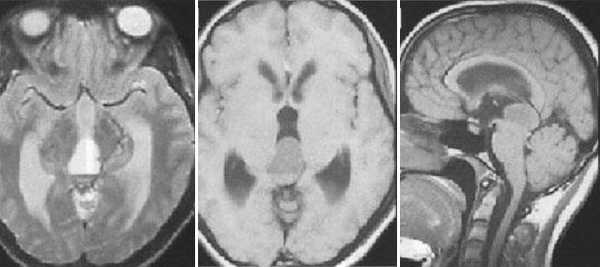

Пинеобластома. В режиме Т2 и Т1 выявляется опухоль задних отделов III желудочка мозга с развитием окклюзионной гидроцефалии. В строме опухоли небольшой участок подострого кровоизлияния. После в/в контрастирования опухоль интенсивно и достаточно гомогенно накапливает контрастирующее вещество.

Герминома пинеальной области. На Т2 ВИ опухоль имеет слабо гиперинтенсивный сигнал по сравнению с тканью мозга, тогда как на Т1 опухоль практически изоинтенсивна с мозгом. Желудочковая система гидроцефально расширена. III желудочек деформирован. Четверохолмная пластинка оттеснена кзади.

Герминома пинеальной области. Опухоль имеет гетерогенное строение с множеством мелких и крупных кист. Вокруг опухоли определяется перифокальный отек.